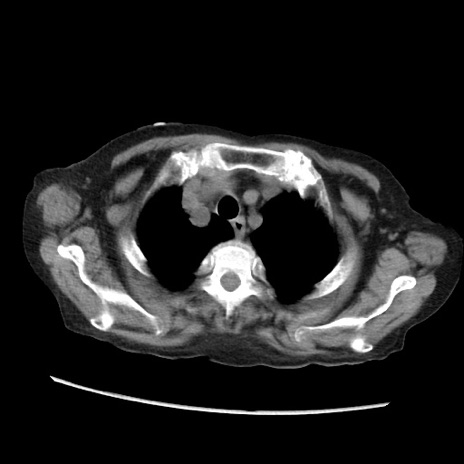

冠状断像

【症例】80歳代 女性

【主訴】腹部膨満感

【現病歴】他院にて肝硬変にてフォロー中。1週間前から便秘、腹部膨満感、臍部腫瘤あり受診となる。

【既往歴】肝硬変

【身体所見】腹部膨隆あり、皮膚変化なし、疼痛なし。

【データ】WBC 4600、CRP 0.25